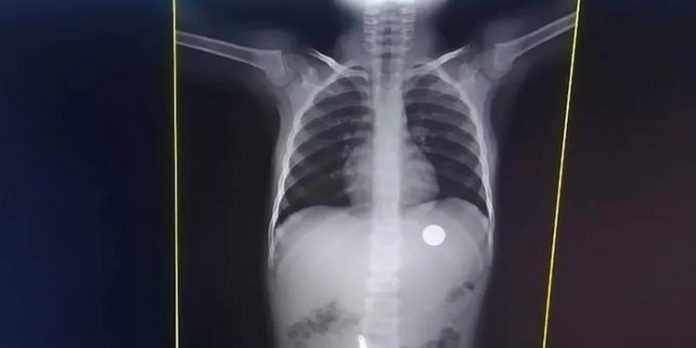

A menina fez uma radiografia, que apontou onde estava a moeda. “Como era menor, não houve necessidade de internação. Se fosse maior, ela teria que passar por uma endoscopia, segundo a médica”, afirmou Karollayne.